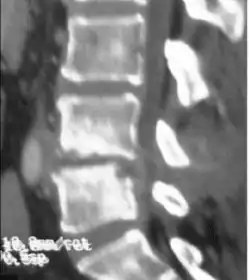

Diagnosis is usually apparent on MRI although plain X-rays and CT examinations can be suggestive. The MRI will reveal air changes in the disc and possibly even external involvement involving the bone or epidural regions. A biopsy may be performed and helps with diagnosis in some cases but often an organism is not obtained. C-reactive protein levels and ESR levels will be elevated and are useful for treatment. Often, the white blood cell count will be normal and the patient will be afebrile.

Discitis with anterior abscess (and disc space abscesses)